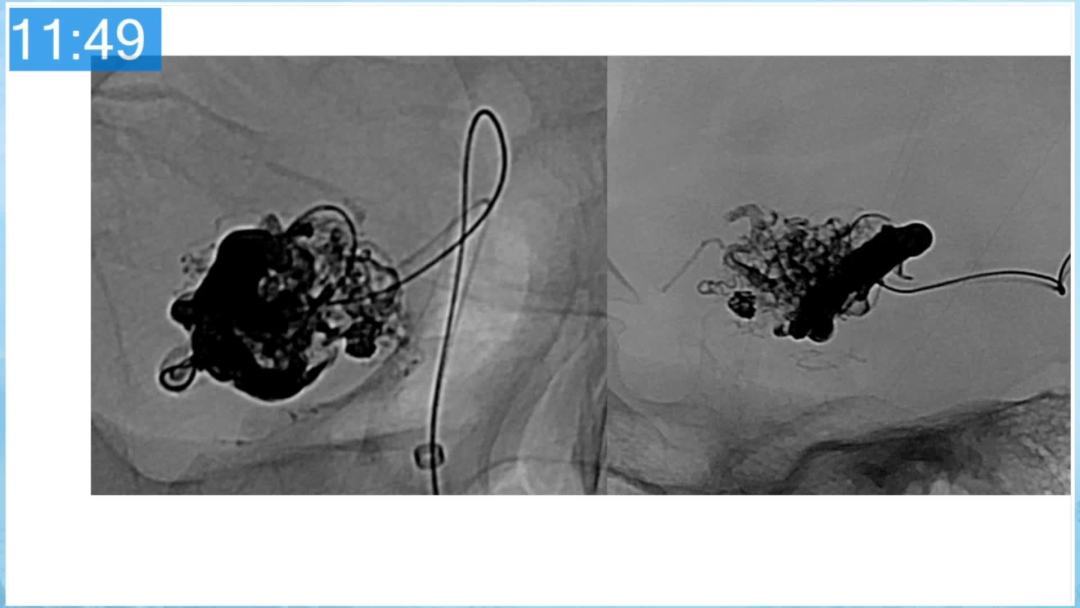

合理的复合平台下的综合治疗,针对每一个病变对应不同方法安全性分析,不预设、不排斥,每种技术发挥到最佳,互相保障。

本期为大家特别分享:空军军医大学唐都医院邓剑平教授的精彩会议内容《颅内动静脉畸形的复合手术治疗》,欢迎大家阅读和分享!